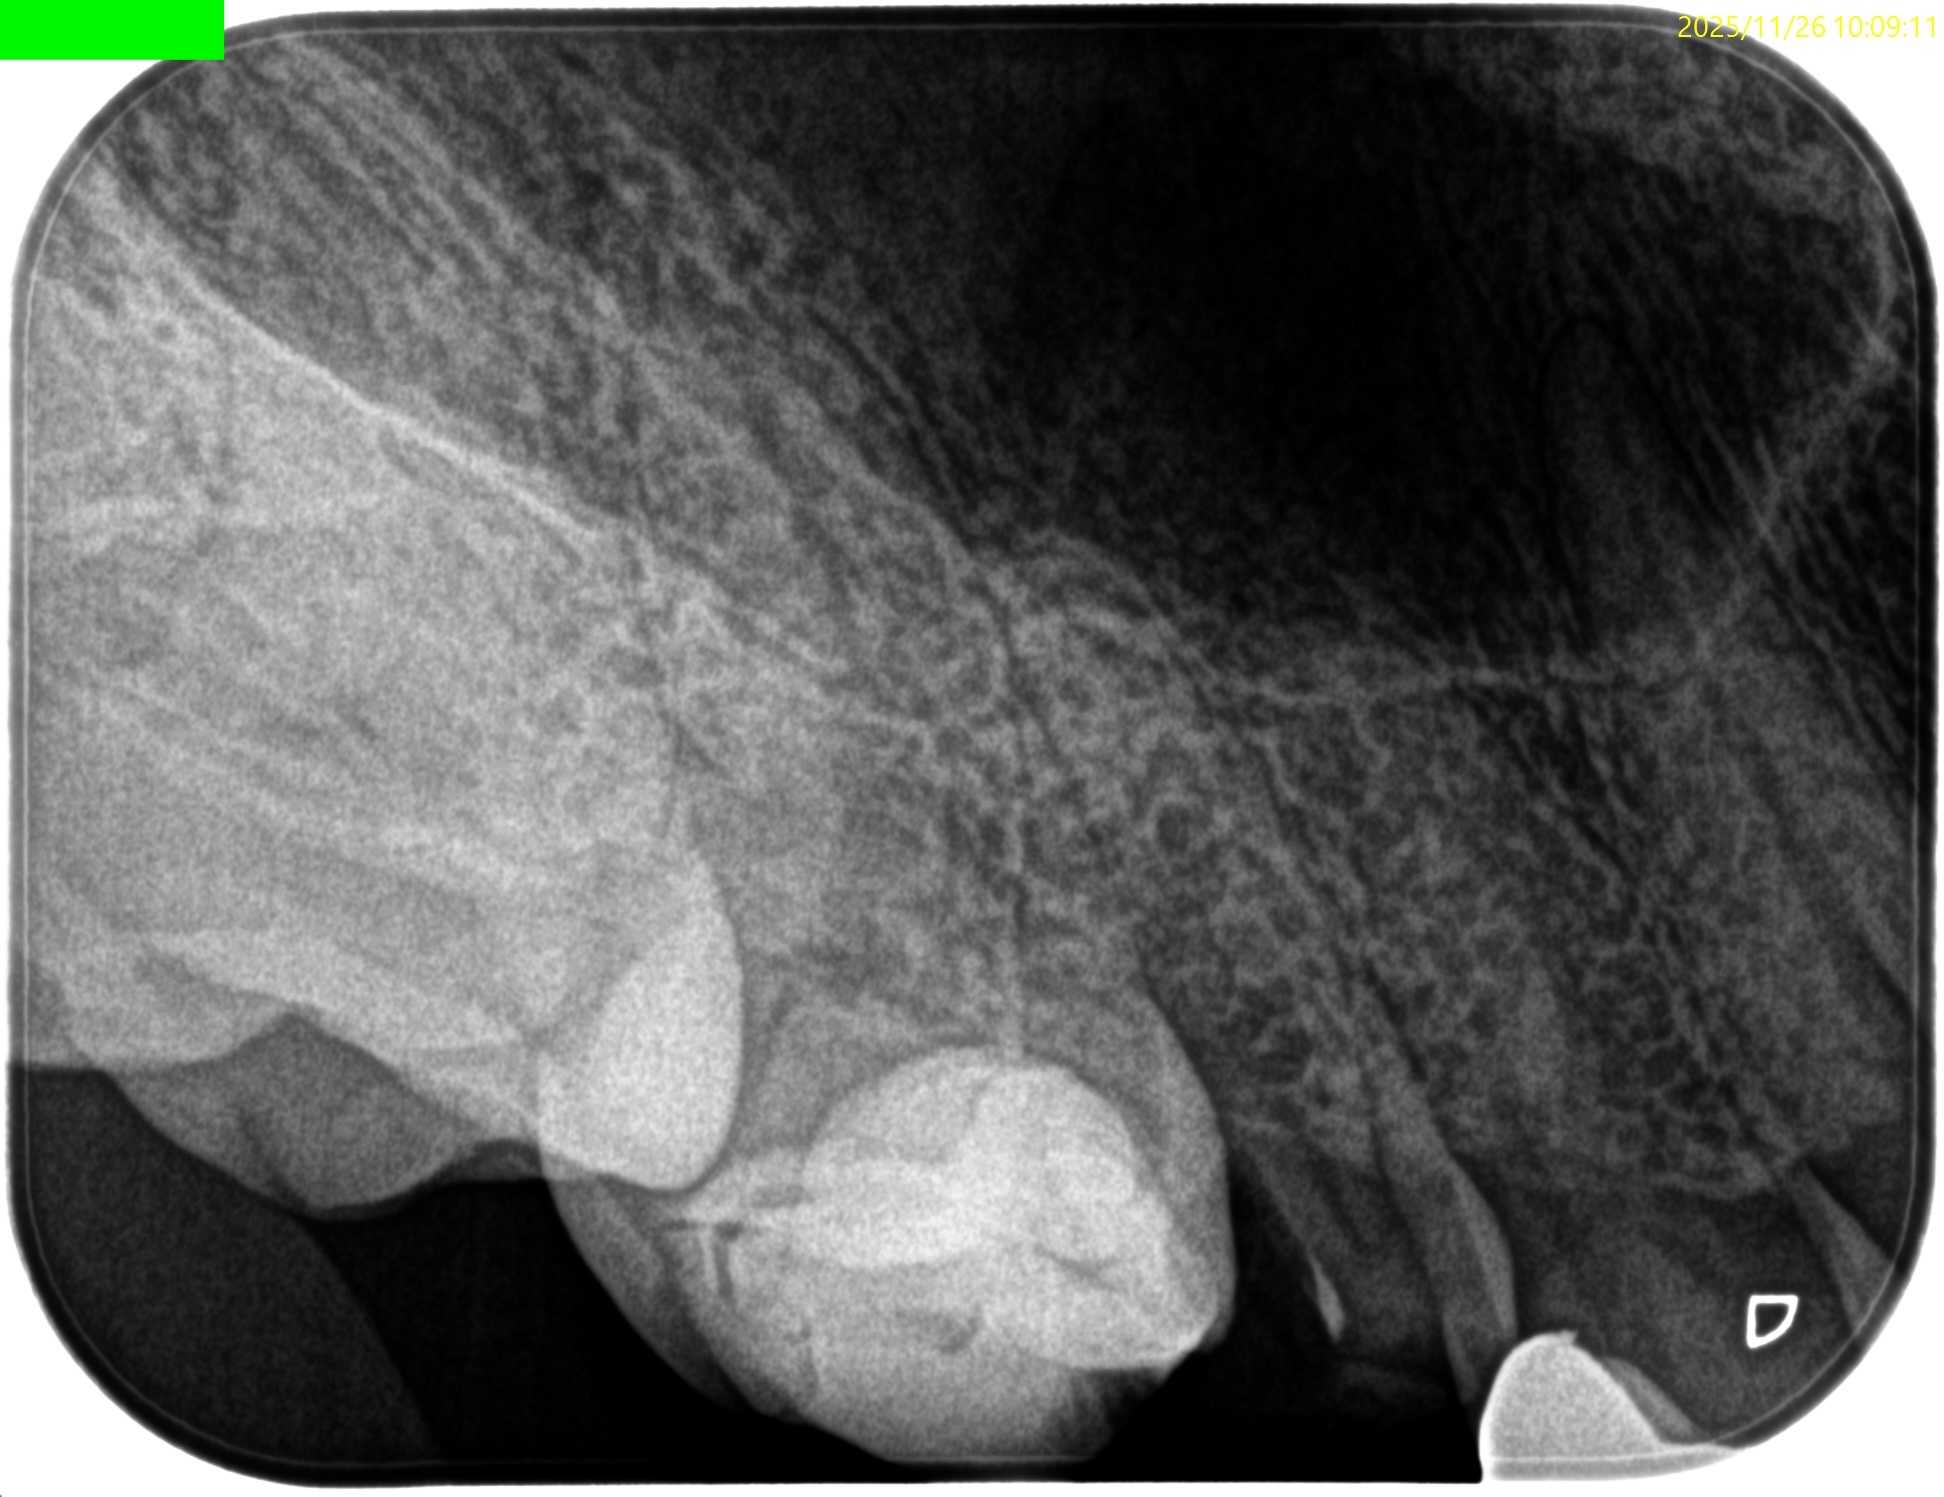

Pre-op Endo test(2025.11.26)

病変のない、Initial RCTだ。

Pulp Dx: Asymptomatic irreversible pulpitis

Periapical Dx: Symptomatic apical periodontitis

Recommended Tx: RCT

術後にPA, CBCTを撮影した。